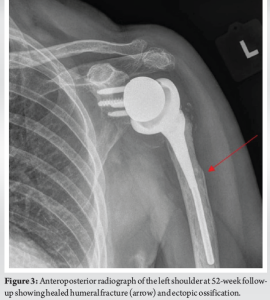

At 4-week follow-up, the patient reported improved arm pain and no longer had pain at night. She had discontinued icing and acetaminophen. Mild tenderness was noted over the mid-humerus fracture site, but she demonstrated satisfactory functional range of motion in abduction and rotation. She was neurologically intact and had full strength. Radiographs indicated reactive changes without displacement but minimal fracture healing (Fig. 2). She was advised to continue the same nonoperative plan and to minimize her strenuous activities. The patient was evaluated 14, 22, and 52 weeks after her injury to monitor for fracture healing and to ensure that no further deformation of the stem occurred. The patient demonstrated progressive improvements in pain and range of motion, returning to her usual activities, including housework and walking with her husband, without pain. At 52 weeks, radiographs confirmed complete fracture healing (Fig. 3), and she was released from our care with no further need for follow-up.